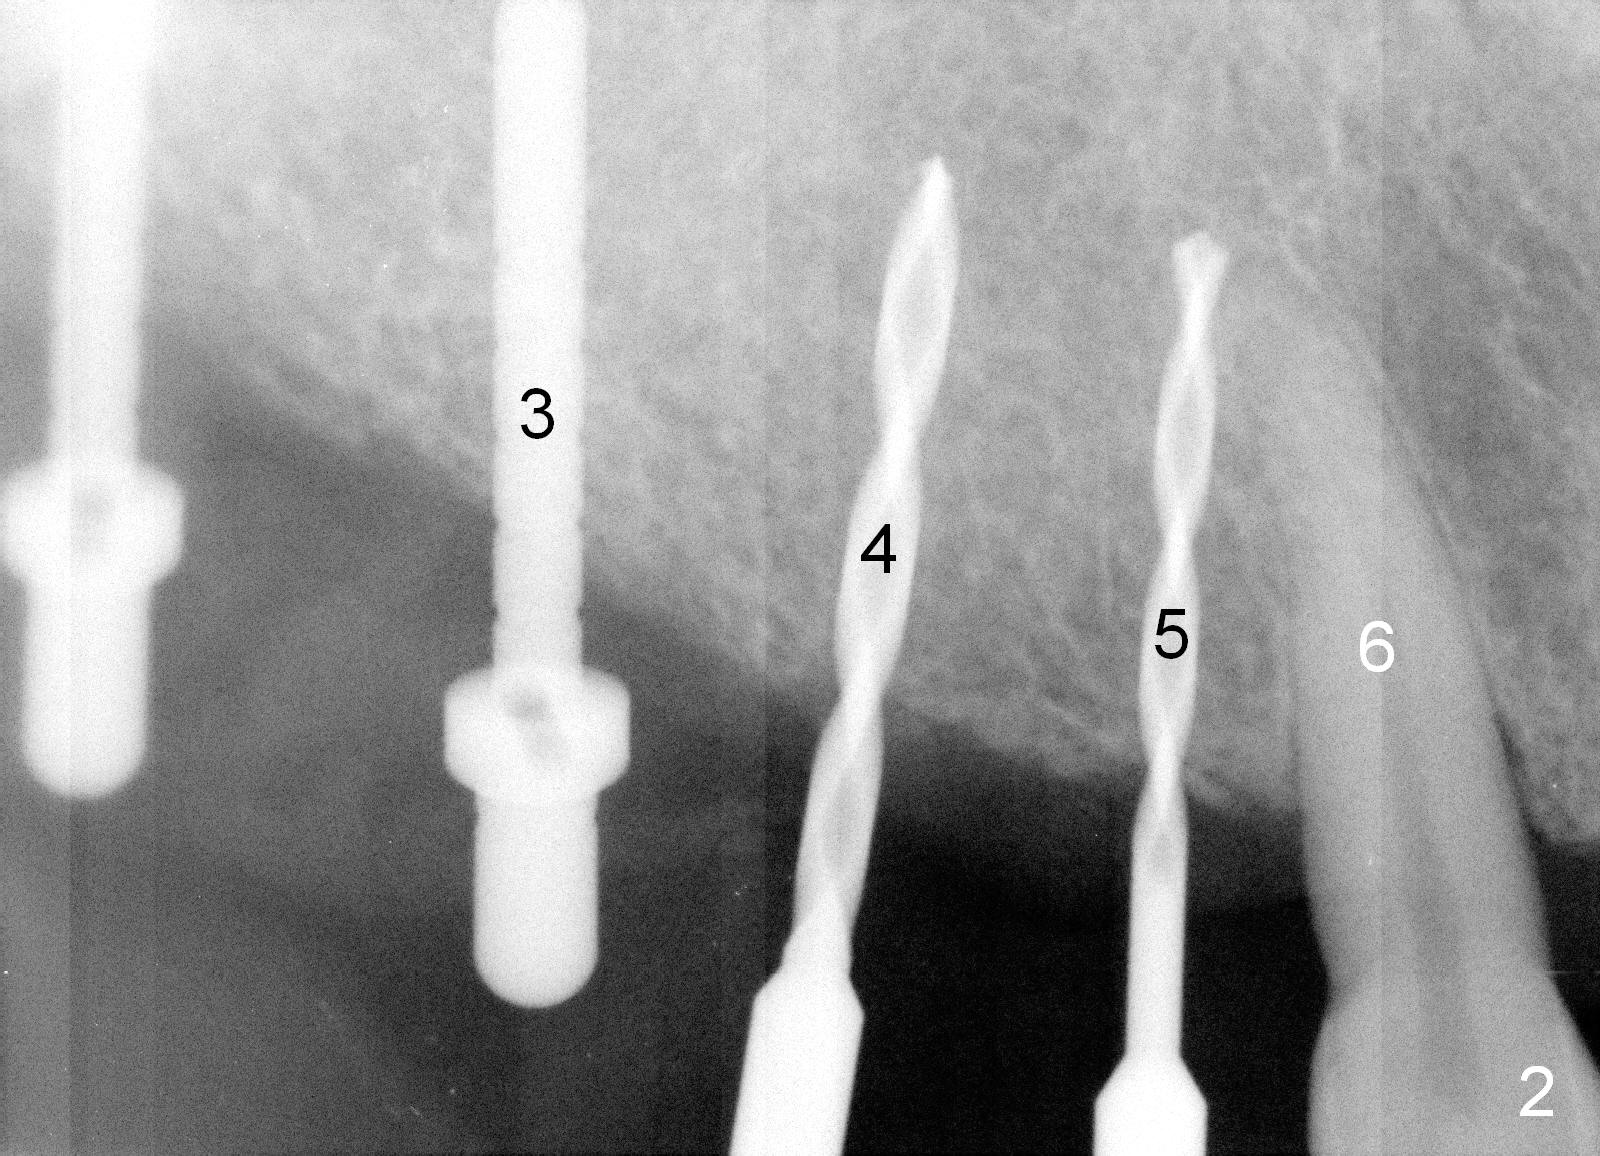

Osteotomy in the upper posteriors starts through a surgical stent for 12 mm.  After incision, each osteotomy is examined, adjusted and extended 2 mm shy of intended (Fig.1,2).  It appears that the trajectories at #4,5 are off (Fig.2).  After re-adjustment, the trajectories are acceptable (Fig.3 (red dashed line; part of the root of the tooth #6)).  Four implants are placed basically in accordance with the plan: 5.9x10 mm at #2, 5x14 at 3, and 3x14 mm 1-piece at 4 and 5 (Fig.4,5).  Fig.6 shows the narrow ridge at #4 and 5 after implant placement.  Although abutments are placed at #2 and 3, an immediate provisional bridge cannot be fabricated because of lack of enough clearance (supraeruption of the opposing dentition).